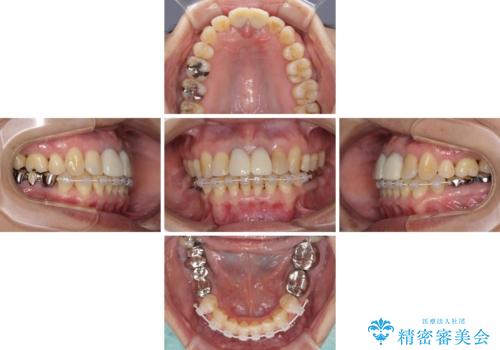

部分矯正とセラミック 前歯の審美治療

- 上の前歯の変色と、下の前歯のデコボコを気にして来院された患者様です。

前歯はオールセラミッククラウンに補綴することとしました。

補綴治療に先立ち、下顎前歯の部分矯正を行い、前歯の咬み合わせの安定性向上を図りました。

相談の上、最も気になっている前歯の部分矯正と補綴治療により口元の改善を図ることとしました。